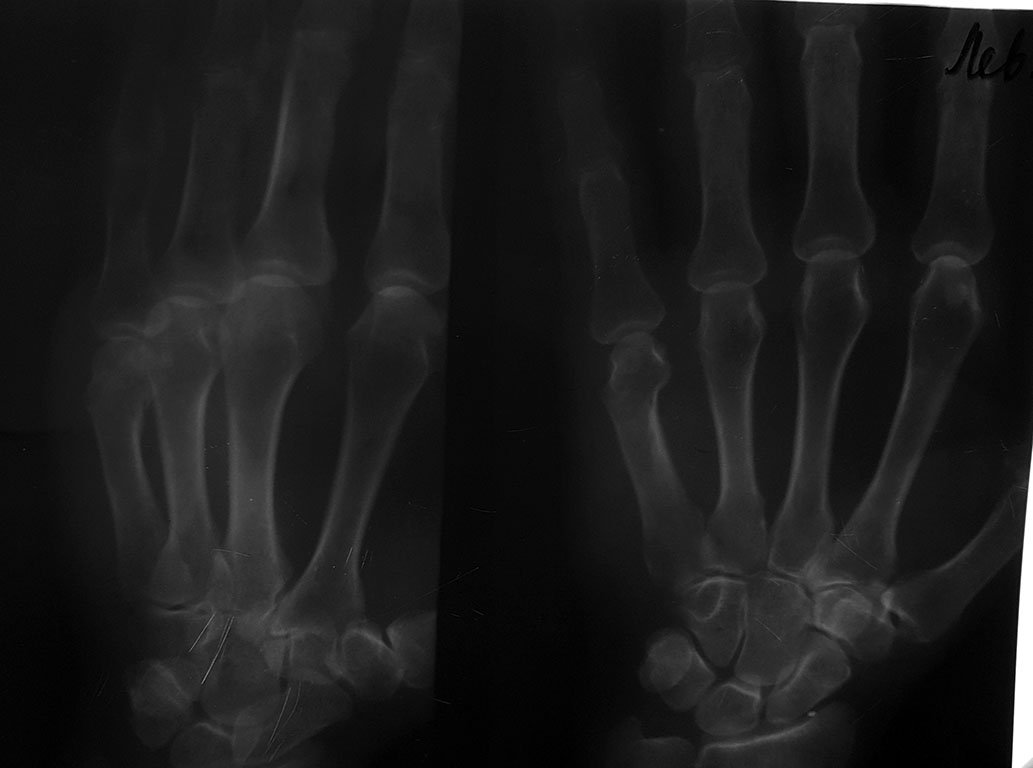

Ну здесь то точно допустимое смещение...

Перелом боксера :) Интересен анамнез :) Оставьте как есть.

Допустимые смещения для разных пястных костей при разных (диаф., субкап.) переломах, но мерять угол можно только в строго боковой проекции

На подвижности это почти никак не отразится. Оперировать не нужно. Если свежий, можно (вероятнее, не нужно) подправить и фиксировать короткой гипсовой или полимерной повязкой. (Не циркулярной, конечно же)

5 пястно-фаланговый сустав очень неприхотлив и угловые смещения мало влияют на функция. Смещение в виде укорочения пястной кости - более заметны. Таким образом: угол 25 гр даст укорочение 1,25, если сминается ладонный кортикальный слой, то укорочение может увеличится до 1.75- 2.0 мм. Это косметический дефект. Мне кажется. что нужно оценивать: 1. Укорочение. 2 Угол смещения.

В среднем допустимые смещения для 5 пястной кости: в сагиттальной плоскости - 30 градусов, хотя Хантер с компаньоном считает и до 70 ничего, по поперечнику не больше половины поперечника, во фронтальной плоскости - 10-15 градусов, по длине - 3-5 мм, ротационные - 0 градусов. Чем дистальнее перелом, тем больше допустимый угол смещения.